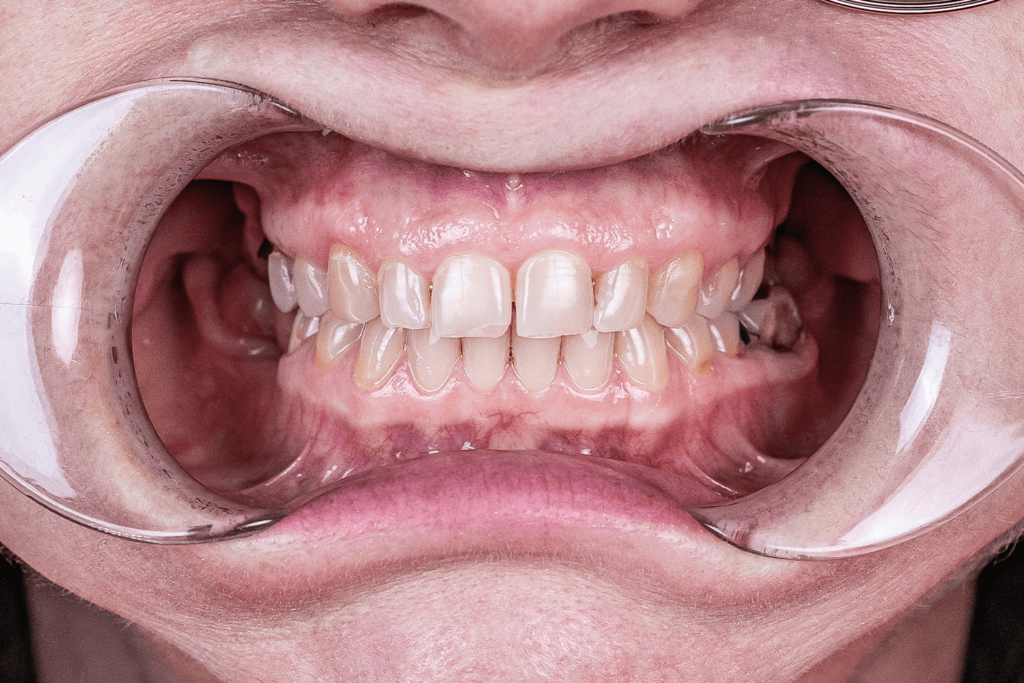

К нам обратилась пациентка с жалобой на отсутствие нескольких зубов и жалобой на патологическое стирание зубов. В результате стирания у пациентки регулярно образовывались сколы на пломбах. Общая ситуация с состоянием зубов и частые небольшие реставрации, которые приходилось выполнять врачам, не удовлетворяли пациентку и она решилась на кардинальные изменения, а именно — устранить все имеющиеся проблемы полости рта более эстетическим и долговечным методом.

- покрыть зубы керамическими коронками и винирами и сразу поднять прикус ортопедическим методом.